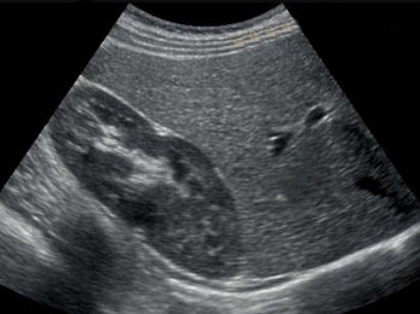

Es una técnica de imagen con la cual podemos explorar diversas estructuras del organismo gracias al uso del ultrasonido.

Los ecógrafos de última generación nos entregan imagenes con muy buena resolución, gracias a ello, no es necesario realizar exámenes de imagen directa como la laparoscopia o histeroscopia.